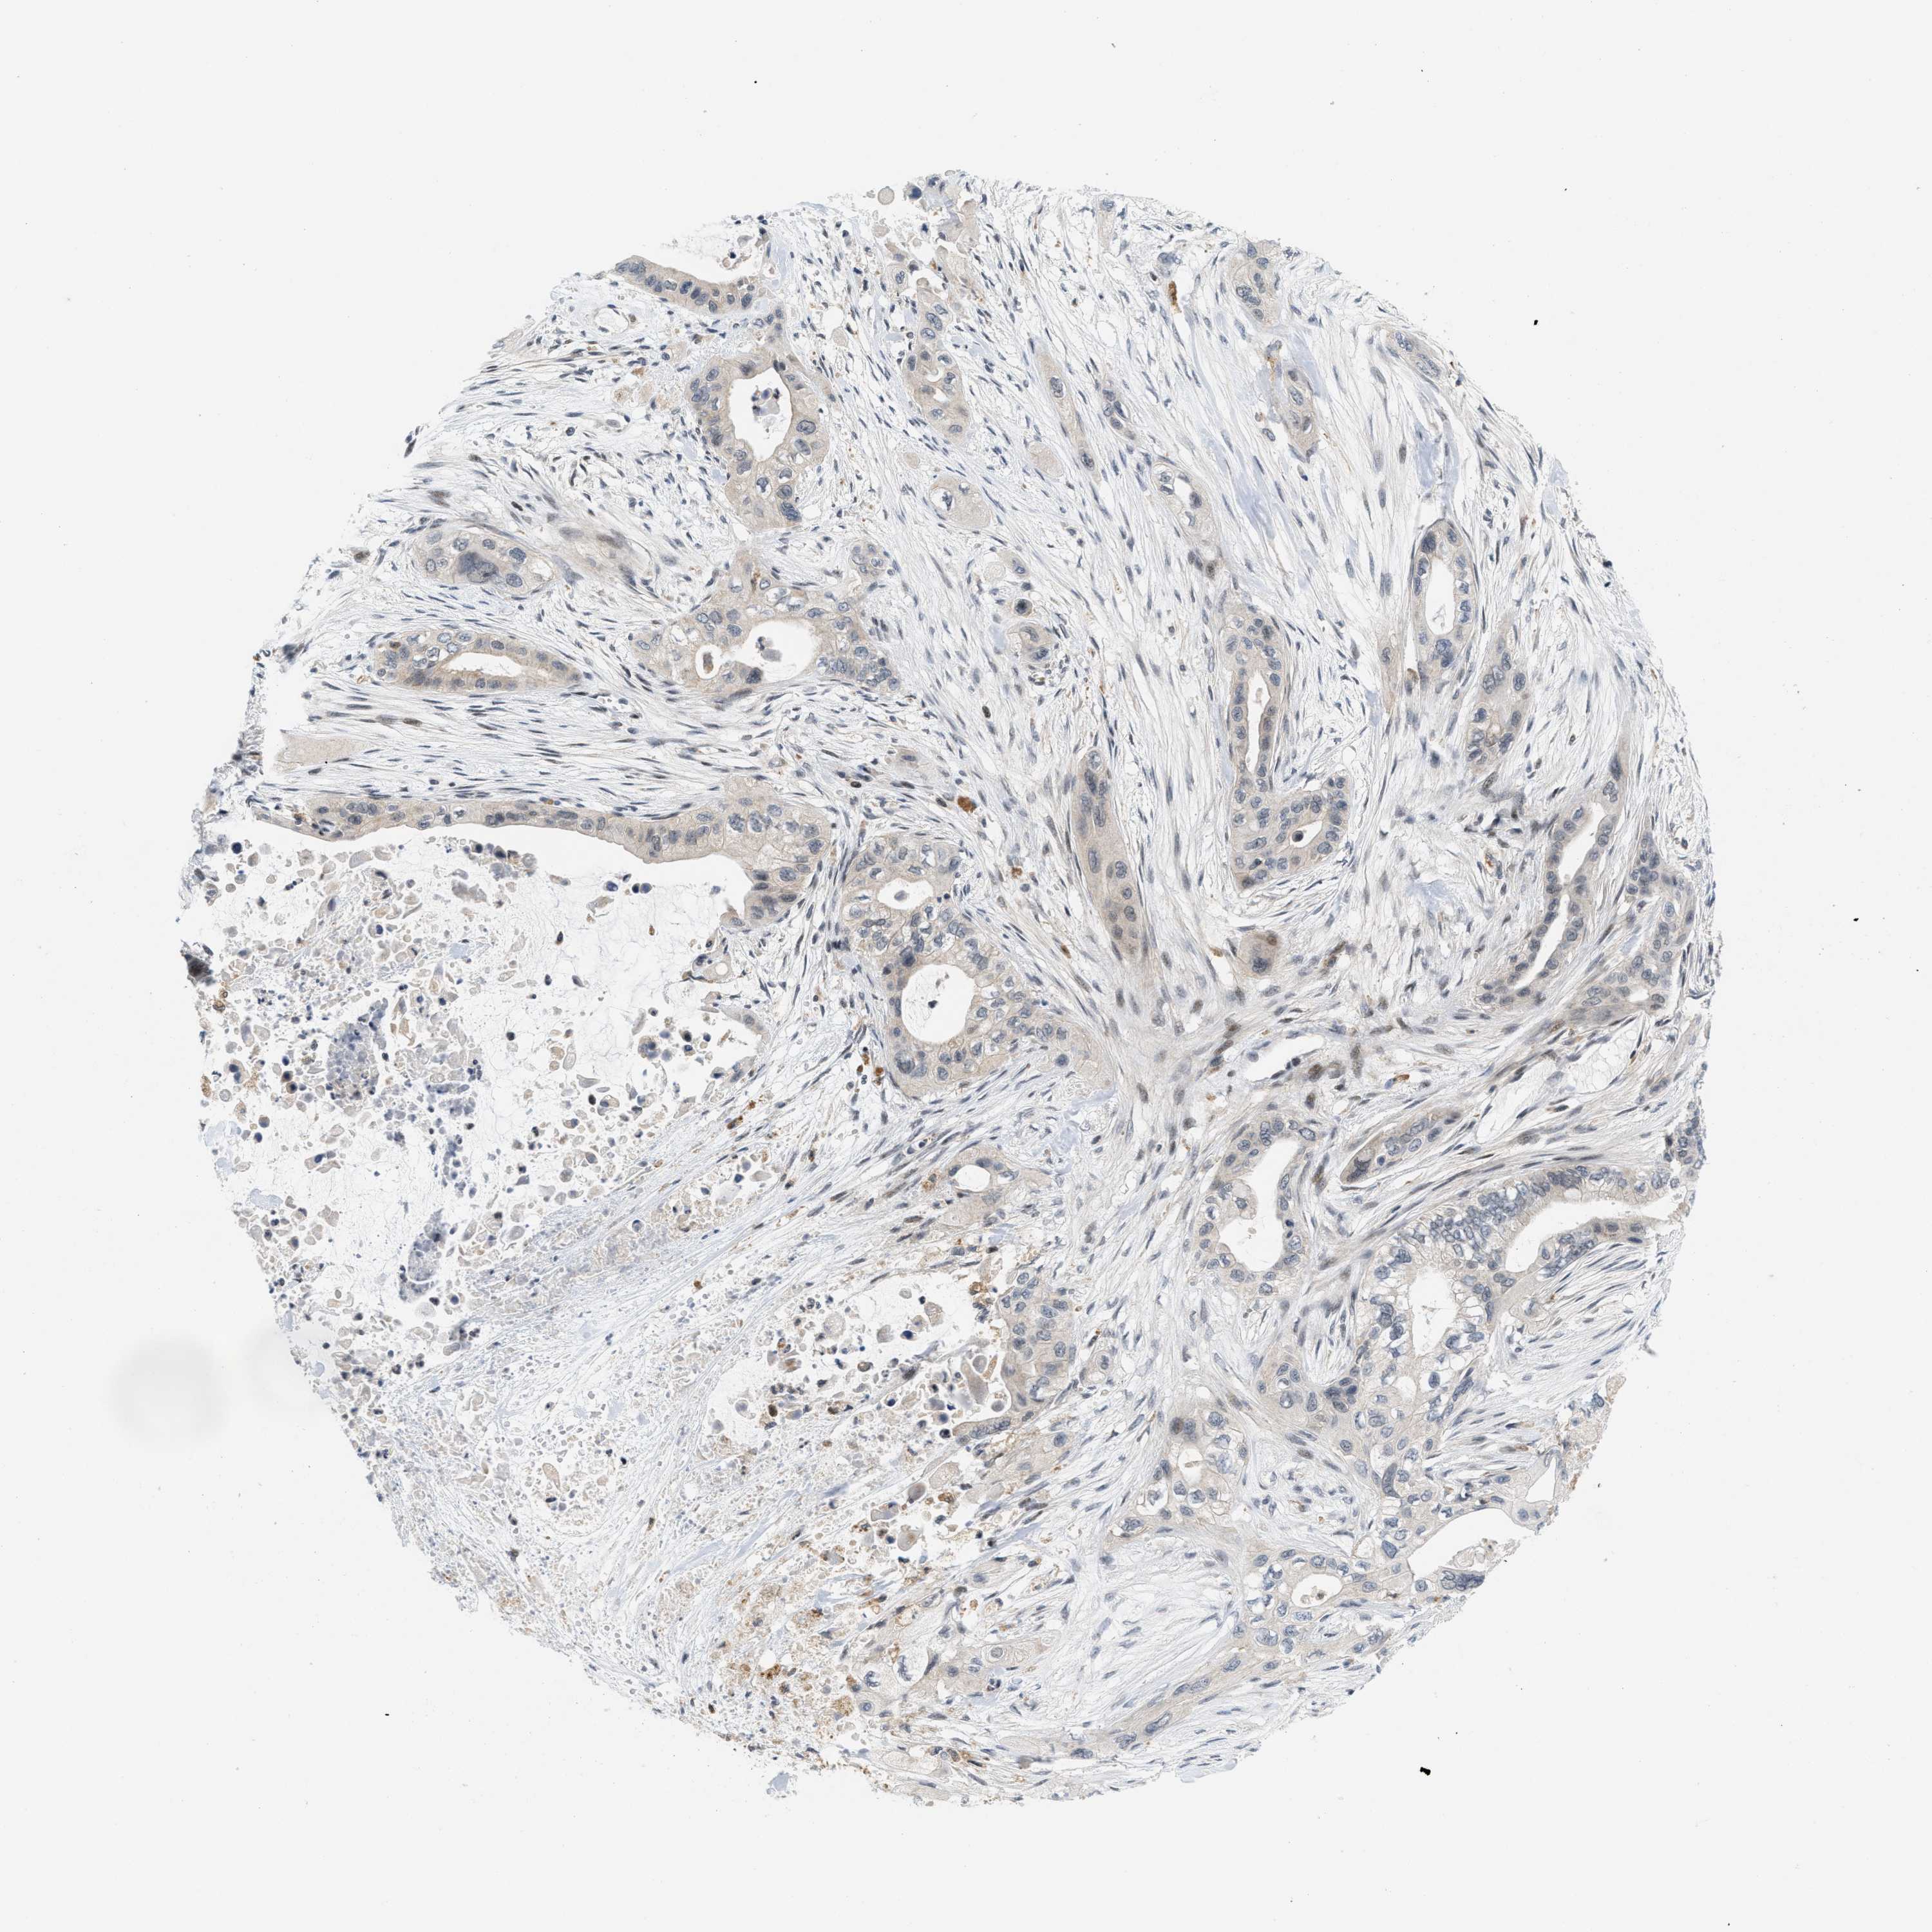

PANCREATIC CANCER - Protein expressioni

A mouse-over function shows sample information and annotation data. Click on an image to view it in a full screen mode. Samples can be filtered based on level of antibody staining by selecting one or several of the following categories: high, medium, low and not detected. The assay and annotation is described here.

Note that samples used for immunohistochemistry by the Human Protein Atlas do not correspond to samples in the TCGA dataset.

Antibody stainingi

Antibody staining in the annotated cell types in the current human tissue is reported as not detected, low, medium, or high, based on conventional immunohistochemistry profiling in selected tissues. This score is based on the combination of the staining intensity and fraction of stained cells.

Each image is clickable and will lead to virtual microscopy that enables deeper exploration of all samples and also displays staining intensity scores, fraction scores and subcellular localization as well as patient and tissue information for each sample.

Antibody CAB016136

Antibody CAB017773

Staining

High

Medium

Low

Not detected

Intensity

Strong

Moderate

Weak

Negative

Quantity

>75%

75%-25%

<25%

None

Location

Nuclear

Cytoplasmic/membranous

Cytoplasmic/membranous,nuclear

Adenocarcinoma, NOS

Adenocarcinoma, metastatic, NOS